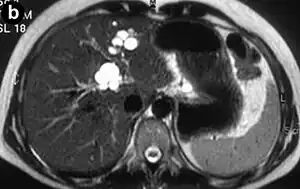

| Turbo spin echo T2-weighted axial MRI of Caroli disease, showing cystic dilatations of bile ducts (shown as white).[1] | |

Magnetic resonance cholangiopancreatography (MRCP) of Caroli disease, showing cystic dilatations of bile ducts.[1]

Modern imaging techniques allow the diagnosis to be made more easily and without invasive imaging of the biliary tree.[9] Commonly, the disease is limited to the left lobe of the liver. Images taken by CT scan, X-ray, or MRI show enlarged intrahepatic (in the liver) bile ducts due to ectasia. Using an ultrasound, tubular dilation of the bile ducts can be seen. On a CT scan, Caroli disease can be observed by noting the many fluid-filled, tubular structures extending to the liver.[4] A high-contrast CT must be used to distinguish the difference between stones and widened ducts. Bowel gas and digestive habits make it difficult to obtain a clear sonogram, so a CT scan is a good substitution. When the intrahepatic bile duct wall has protrusions, it is clearly seen as central dots or a linear streak.[10] Caroli disease is commonly diagnosed after this “central dot sign” is detected on a CT scan or ultrasound.[10] However, cholangiography is the best, and final, approach to show the enlarged bile ducts as a result of Caroli disease.